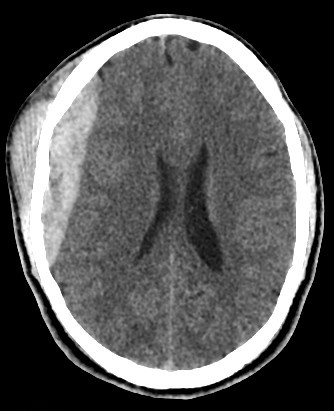

brain CT scan

brain CT scan History

A brain CT scan, also known as a computed tomography scan or CAT scan, is a non-invasive imaging procedure that uses X-rays to create detailed cross-sectional images of the brain and surrounding structures. It's a common diagnostic tool for evaluating head injuries, strokes, brain tumors, and other neurological conditions. Here's a more detailed explanation: What it is: A brain CT scan uses a series of X-ray beams that rotate around the head, capturing multiple images from different angles. These images are then processed by a computer to create detailed cross-sectional views of the brain, allowing doctors to visualize the brain's structures and identify any abnormalities. The scan can be performed with or without contrast dye, which helps to highlight certain tissues and blood vessels for better visualization. Why it's used: Traumatic brain injuries: CT scans are often the first imaging test used to assess the extent of head injuries and identify potential fractures, bleeding, or swelling. Stroke: CT scans can quickly identify whether a stroke is caused by a blood clot (ischemic stroke) or bleeding (hemorrhagic stroke), guiding appropriate treatment. Brain tumors: CT scans can help detect and assess the size and location of brain tumors. Other neurological conditions: CT scans can also be used to diagnose conditions like hydrocephalus (excess fluid in the brain), aneurysms (bulges in blood vessels), and certain types of dementia. Guiding procedures: CT scans can be used to guide biopsies or other procedures involving the brain. What to expect during the procedure: You will lie on a table that slides into the CT scanner, which is a large, doughnut-shaped machine. The scan itself is painless, but some people may experience slight discomfort from lying still on the hard table. If contrast is used, you may feel a warm or flushing sensation, or a metallic taste in your mouth. The scan typically takes only a few minutes. Risks and Precautions: CT scans involve exposure to radiation, but the risk from a single scan is generally considered low. If you are pregnant, it's important to inform your doctor, as alternative imaging methods may be considered to avoid exposing the fetus to radiation. If you have any allergies, particularly to contrast dye, make sure to inform your doctor.